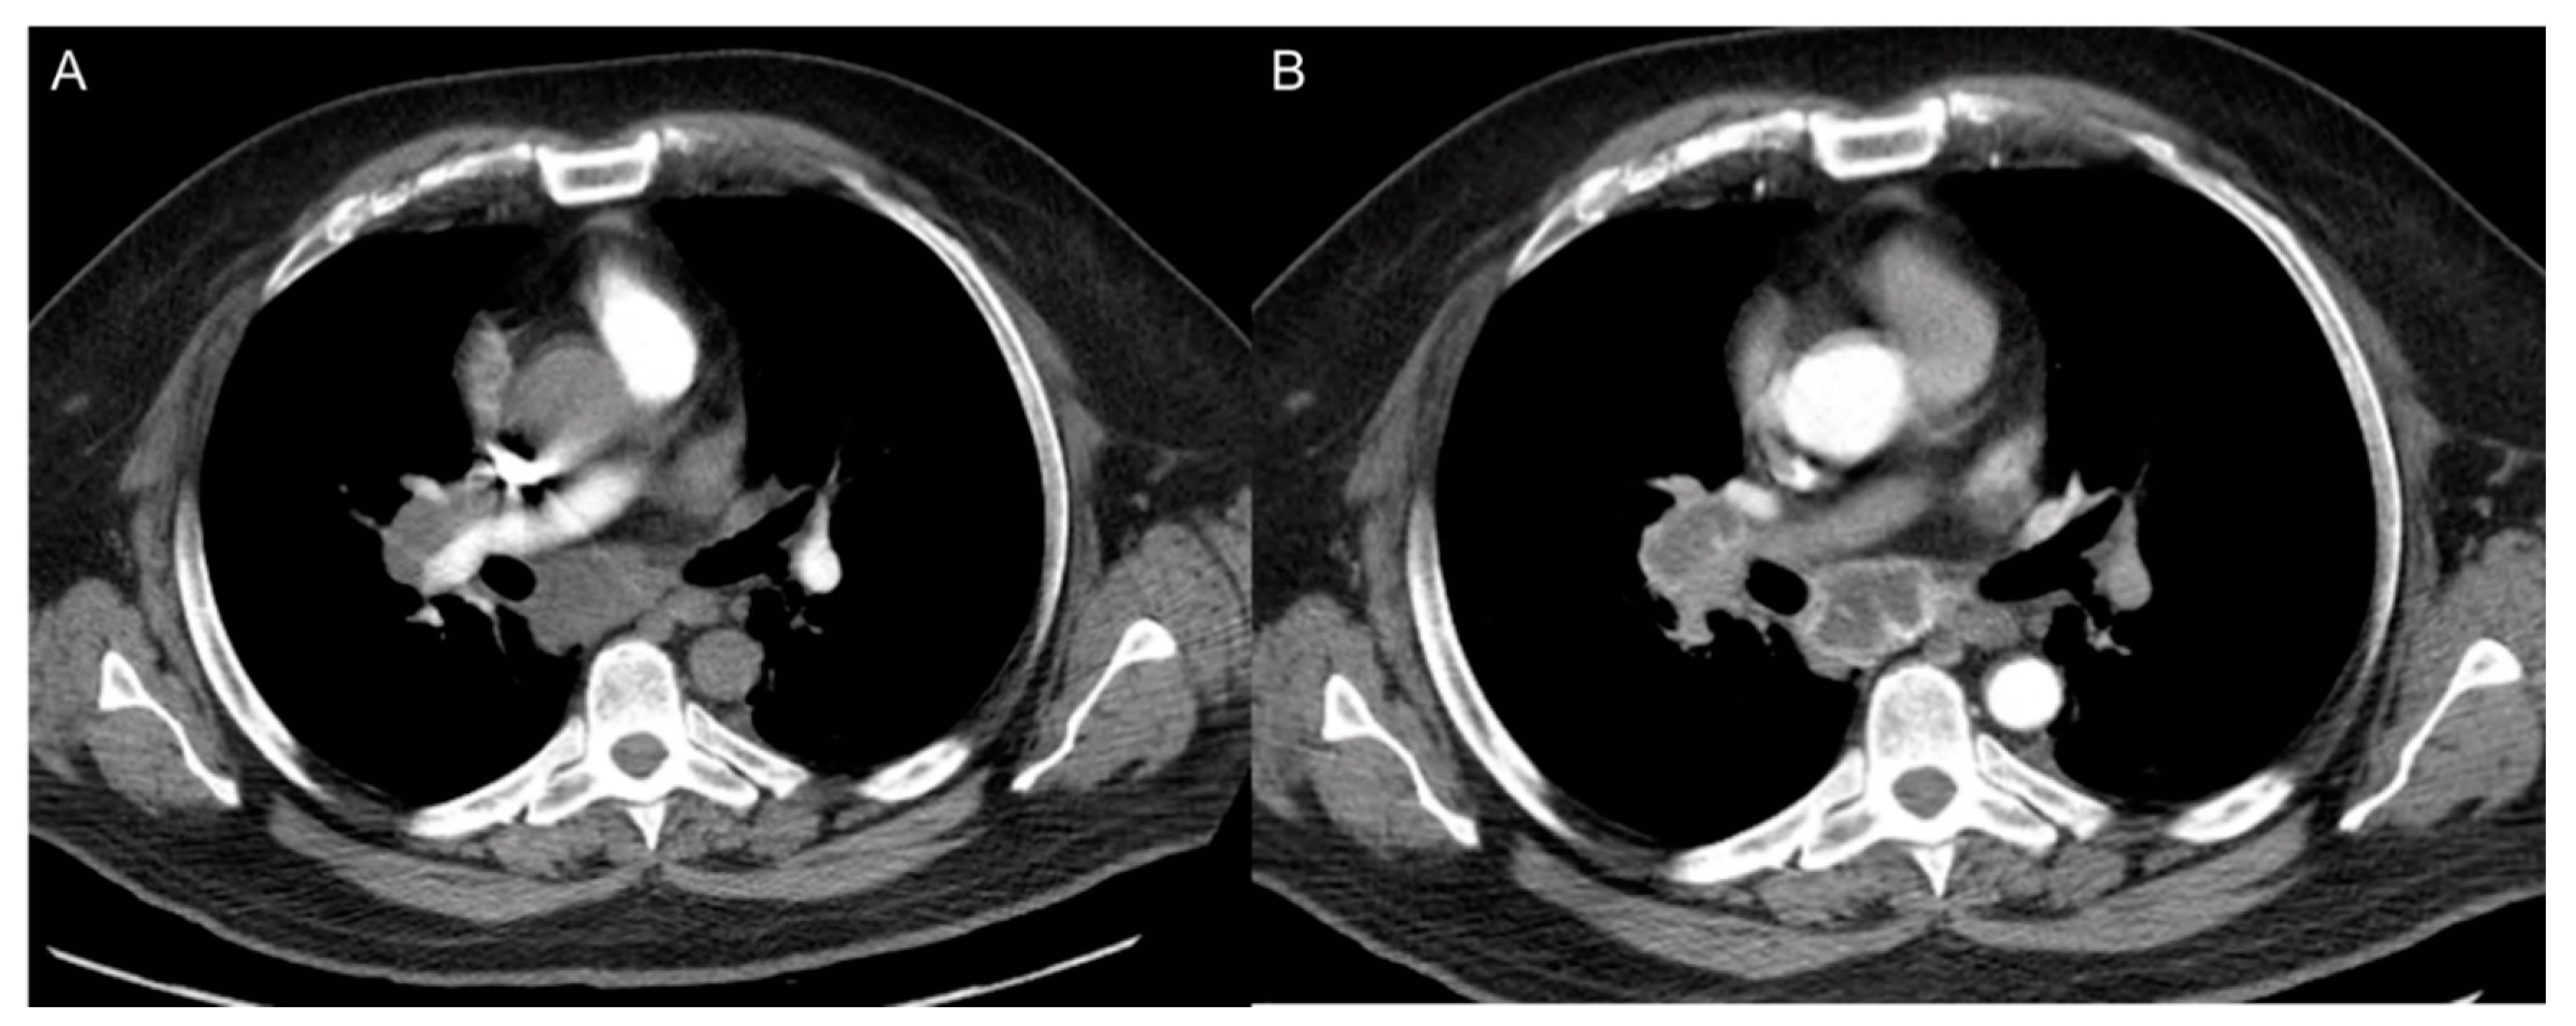

8. CT Imaging of Angiogenesis

8.1. Multi-Slice Computed Tomography (MSCT) Perfusion Imaging Technique

8.2. Clinical Applications of CT Perfusion

- D’Assignies, G.; Couvelard, A.; Bahrami, S.; Vullierme, M.; Hammel, P.; Hentic, O.; Sauvanet, A.; Bedossa, P.; Ruszniewski, P.; Vilgrain, V. Pancreatic endocrine tumors: Tumor blood flow assessed with perfusion CT reflects angiogenesis and correlates with prognostic factors. Radiology 2009, 250, 407–416. [Google Scholar] [CrossRef]

- Xu, N.; Lei, Z.; Li, X.L.; Zhang, J.; Li, C.; Feng, G.Q.; Li, D.N.; Liu, J.Y.; Wei, Q.; Bian, T.T.; et al. Clinical study of tumor angiogenesis and perfusion imaging using multi-slice spiral computed tomography for breast cancer. Asian Pac. J. Cancer Prev. 2013, 14, 429–433. [Google Scholar] [CrossRef] [PubMed]

- Sun, C.H.; Feng, S.; Xiao, P.; Peng, Z.P.; Pui, M.H.; Li, X.H.; Li, Z.P.; Meng, Q.F. Quantitative assessment of perirectal tumor infiltration with dynamic contrast-enhanced multi-detector row CT in rectal cancer. Eur. J. Radiol. 2011, 80, 279–283. [Google Scholar] [CrossRef]

- Mazzei, F.G.; Mazzei, M.A.; Cioffi Squitieri, N.; Pozzessere, C.; Righi, L.; Cirigliano, A.; Guerrini, S.; D’Elia, D.; Ambrosio, M.R.; Barone, A.; et al. CT perfusion in the characterisation of renal lesions: An added value to multiphasic CT. BioMed Res. Int. 2014, 2014, 135013. [Google Scholar] [CrossRef]

- Trojanowska, A.; Trojanowski, P.; Bisdas, S.; Staśkiewicz, G.; Drop, A.; Klatka, J.; Bobek-Billewicz, B. Squamous cell cancer of hypopharynx and larynx—Evaluation of metastatic nodal disease based on computed tomography perfusion studies. Eur. J. Radiol. 2012, 81, 1034–1039. [Google Scholar] [CrossRef] [PubMed]

- Liu, Y.; Bellomi, M.; Gatti, G.; Ping, X. Accuracy of computed tomography perfusion in assessing metastatic involvement of enlarged axillary lymph nodes in patients with breast cancer. Breast Cancer Res. 2007, 9, R40. [Google Scholar] [CrossRef]